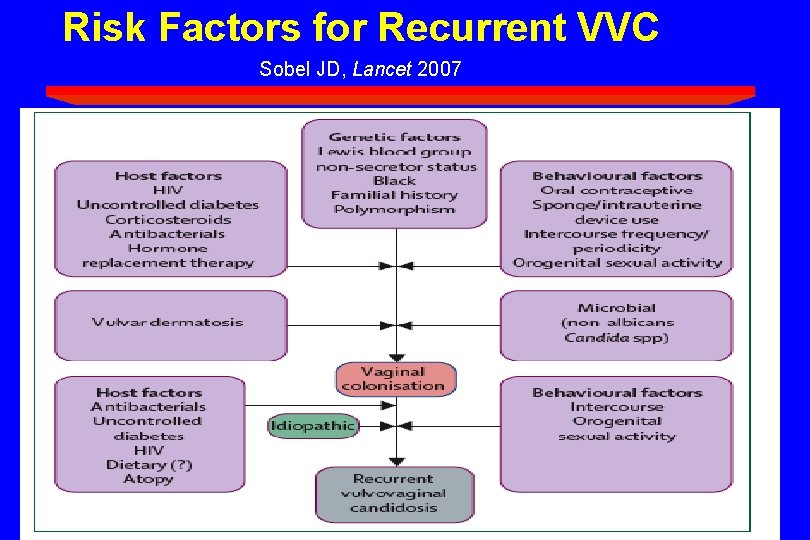

Risk Factors for Recurrent VVC Sobel JD, Lancet 2007